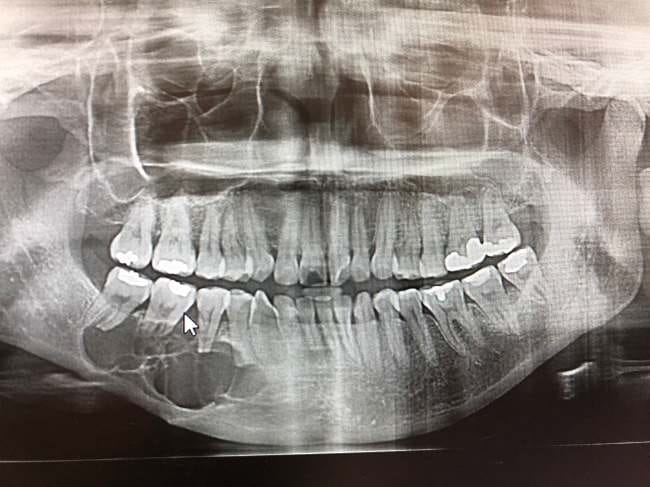

Dokter akan melakukan tanya jawab terkait gejala yang dialami dan riwayat kesehatan pasien. Setelah itu, dokter akan melakukan pemeriksaan pada gigi dan area rahang secara menyeluruh.

Untuk memastikan diagnosis, dokter akan melakukan beberapa pemeriksaan lanjutan berikut:

- Foto Rontgen, untuk melihat lokasi dan gambaran awal tumor

- CT scan atau MRI rahang, untuk mengetahui ukuran tumor serta seberapa jauh penyebarannya